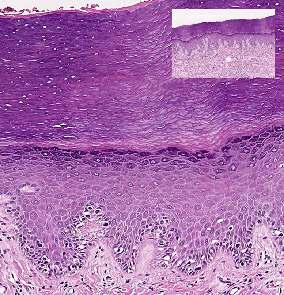

آناتومی پوست و نقش هر لایه در بازسازی سلولی

بازسازی سلولها عمدتاً در اپیدرم اتفاق میافتد، اما لایههای دیگر نیز نقش پشتیبانی دارند:

اپیدرم: محل تقسیم سلولهای بازال و آغاز چرخه.

درم: تأمین مواد مغذی و اکسیژن از طریق مویرگها.

هیپودرم: ذخیره انرژی و ایجاد محیط حمایتی.

مراحل چرخه بازسازی سلولها

- تولید سلول جدید (Proliferation): در لایه بازال اپیدرم، سلولهای بنیادی کراتینوسیتی تقسیم میشوند.

- تمایز (Differentiation): سلولها به سمت لایههای بالاتر حرکت میکنند و کراتین تولید میکنند.

- مرگ برنامهریزیشده (Apoptosis): سلولها در لایه شاخی میمیرند و به سلولهای شاخی (Corneocytes) تبدیل میشوند.

- ریزش سلولهای مرده (Desquamation): سلولهای قدیمی جدا میشوند و جای خود را به سلولهای تازه میدهند.